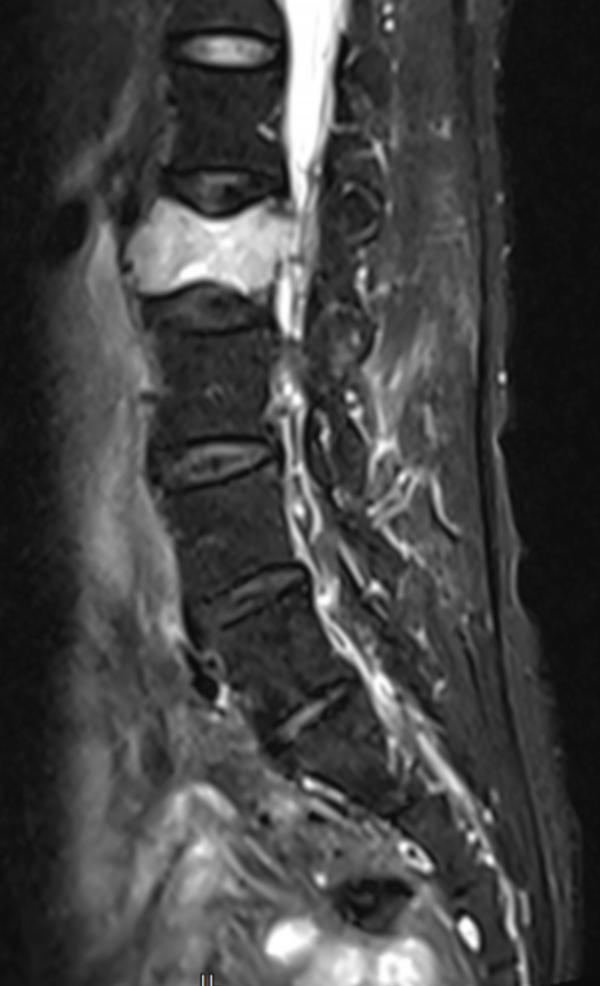

文章配圖

△ 術前MRI:腰2椎體骨質破壞,考慮腫瘤性病變。